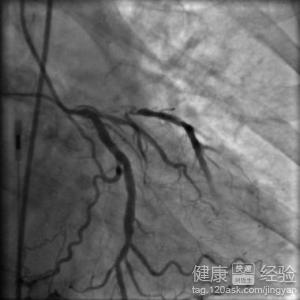

3第三,心髒冠狀動脈血管成像CT(CTA),冠脈造影:若患者出現胸悶、胸痛不適,且活動後逐漸加重,可能有心梗復發,可行CTA檢查,若是觀察不明確,可行冠脈造影檢查,進一步明確病因。

第3步